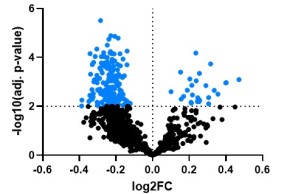

Project 3: Identification of novel disease genes for monogenic forms of early-onset low BMD disorders

Project 3 utilizes high-throughput sequencing technologies to discover novel disease genes for primary early-onset low bone mineral density disorders. For each newly identified monogenic disease gene, specific combinations of clinical features, osteologic parameters, immunologic and/or metabolic changes in affected individuals will be identified. Functional studies are performed to confirm the pathogenicity of the genetic variants and to investigate the pathomechanism.

Central Project 2: Bioinformatic data integration and multi-omic pathway analysis

CP2 will offer bioinformatics support for every stage of the computational analysis of clinical and omics data generated in the ProBone project, this includes sample collection, experimental design, harmonized data analysis, and hypothesis generation and validation. CP2 will concentrate on identifying patient subtypes in early-onset low BMD disorders and the disease mechanisms that differentiate these subtypes.